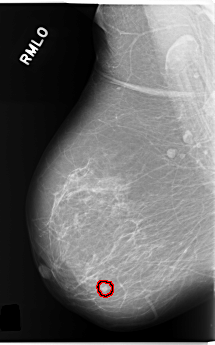

C_0253_1.RIGHT_MLO

FILE: C_0253_1.RIGHT_MLO.OVERLAY

TOTAL_ABNORMALITIES 1

ABNORMALITY 1

LESION_TYPE CALCIFICATION TYPE PUNCTATE DISTRIBUTION CLUSTERED

LESION_TYPE MASS SHAPE OVAL MARGINS CIRCUMSCRIBED

ASSESSMENT 4

SUBTLETY 5

PATHOLOGY BENIGN

TOTAL_OUTLINES 1

BOUNDARY